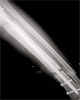

Follow Up

Good bony union with preservation of bone length

excellent outcome with good range of knee and ankle motion.Patient returned to normal activities